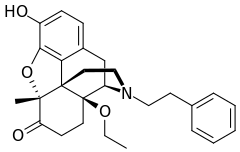

Several semi-synthetic opioids were developed in Germany in the 1910s. The first, oxymorphone, was synthesized from thebaine, an opioid alkaloid in opium poppies, in 1914.[228] Next, Martin Freund and Edmund Speyer developed oxycodone, also from thebaine, at the University of Frankfurt in 1916.[229] In 1920, hydrocodone was prepared by Carl Mannich and Helene Löwenheim, deriving it from codeine. In 1924, hydromorphone was synthesized by adding hydrogen to morphine. Etorphine was synthesized in 1960, from the oripavine in opium poppy straw. Buprenorphine was discovered in 1972.[228]

- Semi-synthetic opioids: created from either the natural opiates or morphine esters, such as hydromorphone, hydrocodone, oxycodone, oxymorphone, ethylmorphine and buprenorphine;

Semi-synthetic alkaloid derivatives